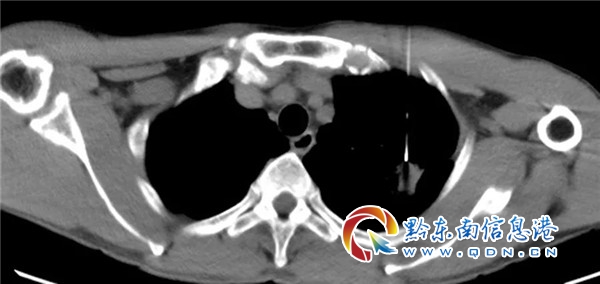

患者袁某某,男,51岁,贵州天柱县人。因“咳嗽、胸闷、胸痛10天”入我院感染科。胸部CT:1.左上肺病灶(结核?肺Ca?直径大小:2.1×1.7cm)伴周围少许炎症,邻近胸膜增厚、粘连。右肺中叶结节;2.纵膈淋巴结显示增多。建议:CT增强及穿刺活检。遂转入胸部肿瘤科,经彭杰博士接诊后,考虑患者肺部肿瘤可能性大。并完善头颅及腹部影像学检查均未见明显转移灶,与患者及家属充分沟通后,由彭杰博士行CT引导经皮肺穿刺活检术。病理示:肺腺癌。初步诊断:左上肺腺癌并纵膈淋巴结转移 (T2N2M0, ⅢA期)。

会议首先由彭杰博士介绍患者病情及相关影像、病理、实验室检查结果,接着南方医院影像中心专家详细解读胸部增强CT结果,胸部纵膈淋巴结及胸膜侵犯均存疑,纵膈淋巴结偏向良性可能,建议PET-CT检查。胸外科专家从外科角度对病人的病情进行分析,建议PET-CT或者E-BUS检查,明确纵膈淋巴结转移情况,胸膜是否累及不能排除,同时也提议可以考虑直接行胸腔镜下肺癌根治术,根据术后结果安排是否辅助治疗。肿瘤放疗专家根据影像考虑胸膜侵犯不能确定,纵膈淋巴结转移N2可能性大,提议完善PET-CT或者E-BUS检查,如果为N2提议根治性同步放化疗。最后经反复讨论及与患者沟通:建议患者先行PET-CT检查,明确肿瘤分期后按分期模式行外科手术或者同步放化疗。患者及家属表示经参会后对肺癌的治疗有了更大的信心。